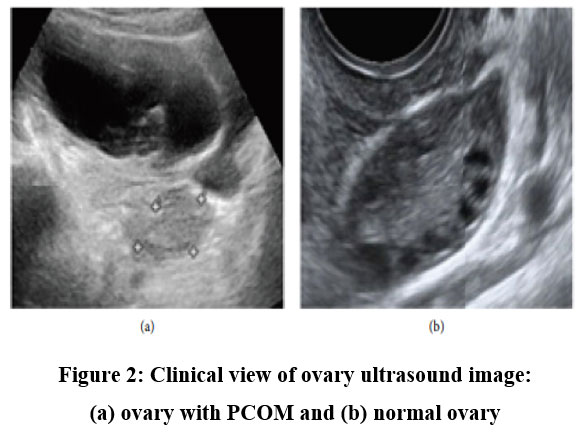

After completing image collection, the process for obtaining clinical data was begun to investigate how clinical data affected the diagnosis of PCOS. This procedure seeks to obtain clinical data for patients whose ultrasound images were gathered in the previous phase from the hospital system. The features were chosen with the assistance of professional judgments and with consideration of previous studies that identified the significance of those attributes on PCOS diagnosis in some manner.11,22 There are many clinical data points that are lacking and need further validation, as we discovered while collecting clinical data for 391 patients whose ultrasound photos were already accessible. Ultimately, a dataset has 285 samples and 22 characteristics. The clinical dataset is composed of 156 non-PCOS individuals and 129 PCOS cases. Diagnoses for patients in the dataset are made using laboratory results, medical records, and radiologist analysis of ultrasound pictures to distinguish between PCOS and non-PCOS. Characteristics are divided into four categories, including demographics, vital signs, lab results, and doctors’ comments, such as cycle regularity. The dataset has two data types, four nominal/categorical features, and 17 numeric features. Additionally, only photos that clearly show the ovary were chosen for the investigation. Radiologists divided the selected images into two categories for categorization: the sonographically visible PCOM and those with a normal morphology (non-PCOM). As seen in Figure 2, PCOM is represented by an ovary with several, uniformly sized, peripherally positioned follicles that are smaller than one centimetre. The dataset of photographs consists of 391 images which has clinical record result of 127 PCOM, and 264 normal ovaries that are not PCOM.

Figure 2: Clinical view of ovary ultrasound image: (a) ovary with PCOM and (b) normal ovaryClick here to view Figure

Four categories can be used to group the characteristics, including demographics, vital signs, laboratory tests, and medical notes. The dataset has two data types, four nominal/categorical features, and 17 numeric features. Additionally, only photos that clearly show the ovary were chosen for the investigation. Radiologists divided the selected images into two categories for categorization: those with a non-PCOM and those displaying the sonographic PCOM. Figure 2 illustrates an ovary with numerous, uniformly sized follicles that are positioned peripherally and have a diameter of less than 1 cm. This is the definition of the polycystic ovarian morphology. 391 pictures, 127 PCOM, and 264 normal ovaries that are not PCOM make up the image dataset.